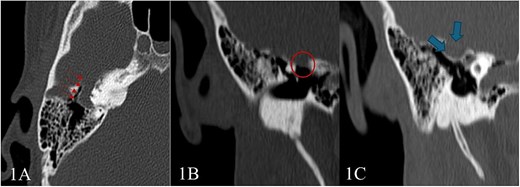

Pure tone audiometry demonstrated mild low-frequency conductive hearing loss in the right ear, while hearing thresholds were within normal limits in the left ear. Given these findings, a high-resolution CT scan of the temporal bones was performed, revealed a tubular lucency lateral to superior semicircular canal with associated dehiscence. Additionally, lateralization of the ossicular chain and apparent subluxation of incudomalleolar joint were observed (Fig. 1). This was associated with an undulating contour suggestive of a possible intracranial component, raising suspicion for a small meningocele or cephalocele—warranting further evaluation with MRI.

High-resolution CT scan of the temporal bone shows: (A) Tubular lucency noted lateral to superior semicircular canal with associated dehiscence. (B and C) Scalloping and protrusion of right tegmen tympani into epitympanum with a marked narrowing of epitympanum recess. Additionally, there is a lateralization of ossicular chain and apparent subluxation of incudomalleolar joint.